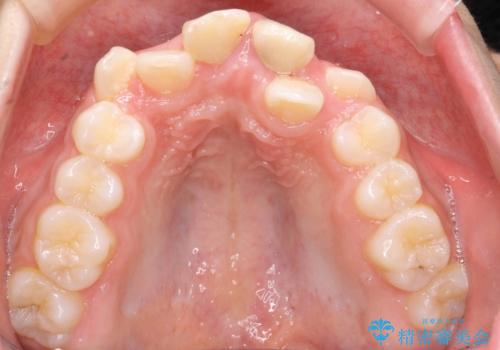

- 前歯のガタガタを主訴に来院。

上の前歯は、小さいころにぶつけて折ったとのことで、神経が死んでおり、根の治療が必要な状態でした。

上下の小臼歯を抜歯しています。

左上の前歯は神経が死んでおり治療が必要な状態でした。また、右上の前歯も根の先に感染がありましたので治療を行いました。

また、プラスチックでつぎはぎになっていたため、虫歯を取りしっかりとしたクラウン(被せもの)としました。